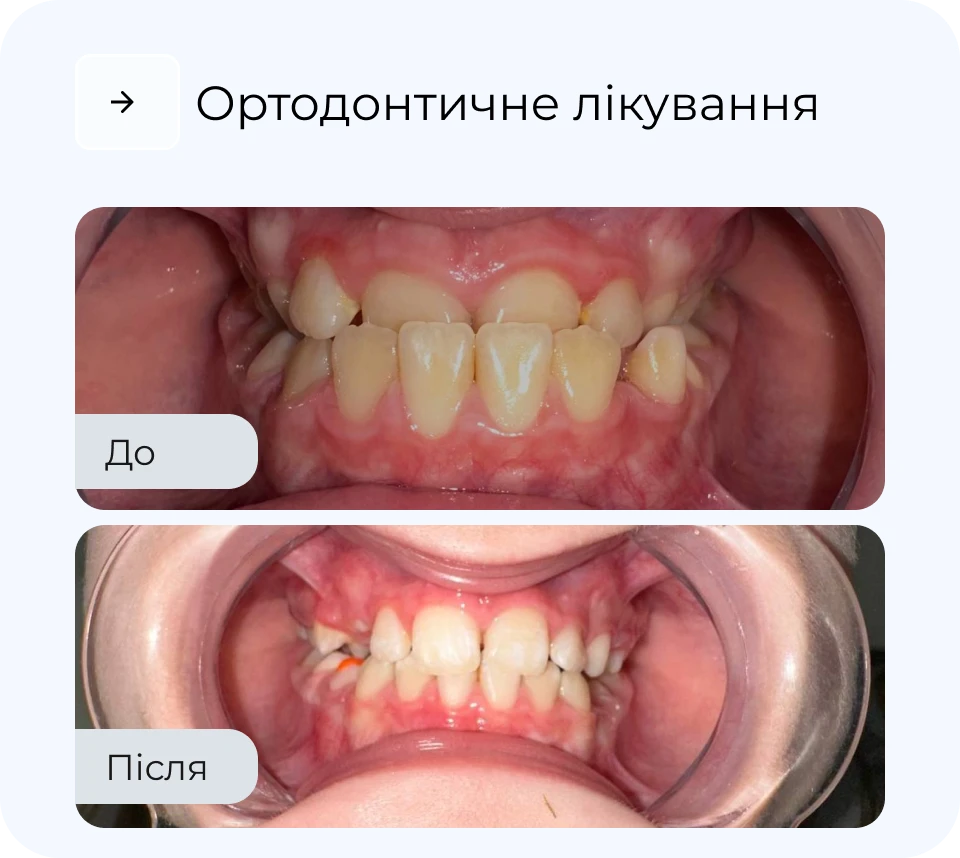

Ортодонтичне лікування дозволяє не лише вирівняти зуби, а й покращити функцію всього щелепного апарату. У MAXI Dent підбирають метод корекції індивідуально — від класичних брекетів до майже непомітних елайнерів. Процес лікування контролюється на кожному етапі, що забезпечує прогнозований результат. Наш підхід — максимально комфортно, естетично і без зайвих втручань.

Наші результати роботи

*тисни, щоб побачити до/після

Результати

*тисни, щоб побачити до/після

Результати

*тисни, щоб побачити до/після